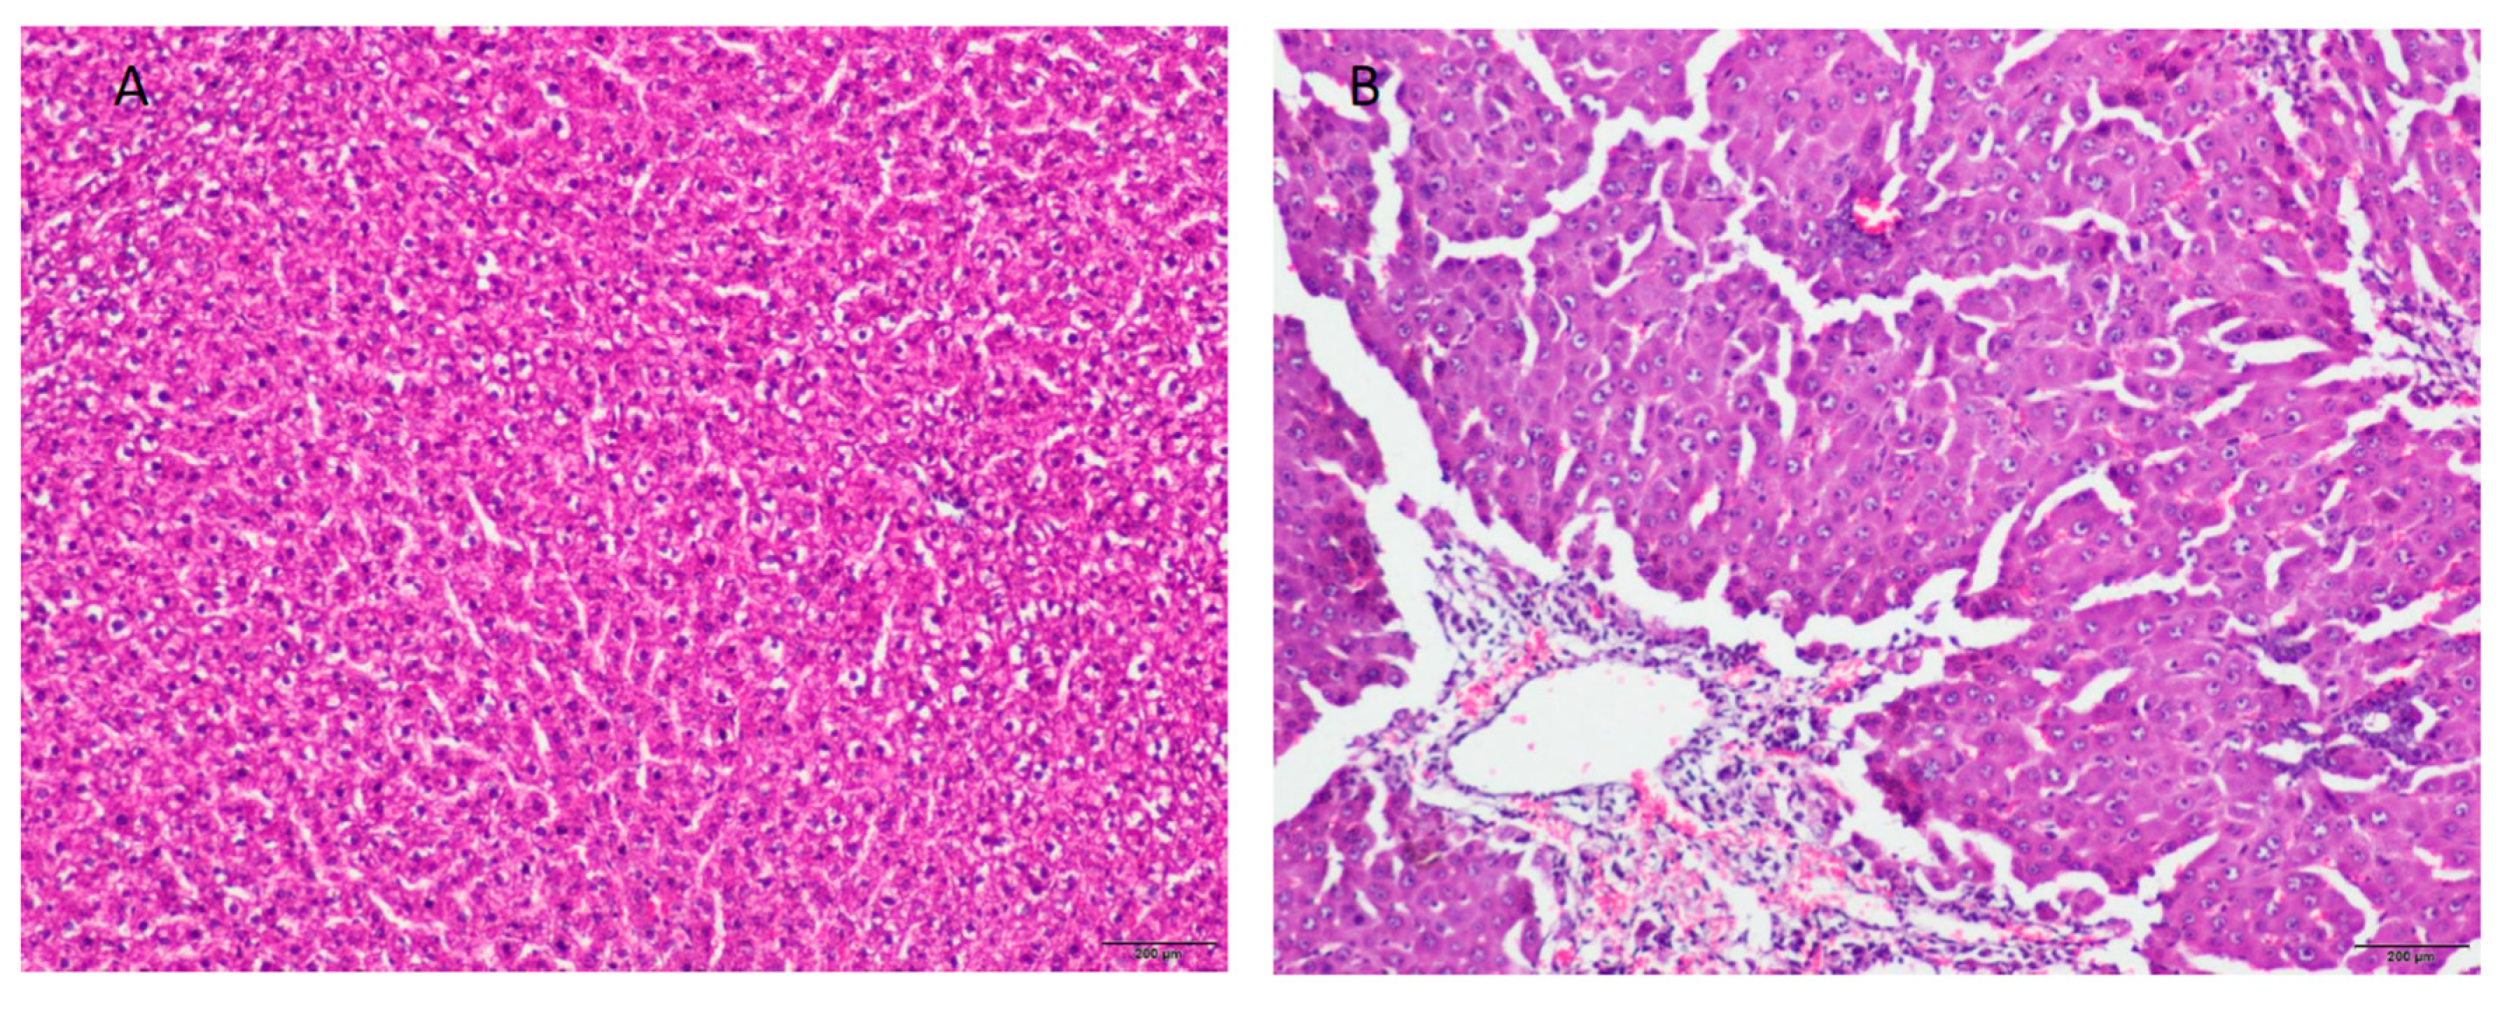

2.1. Rat Model of Acute Liver Failure